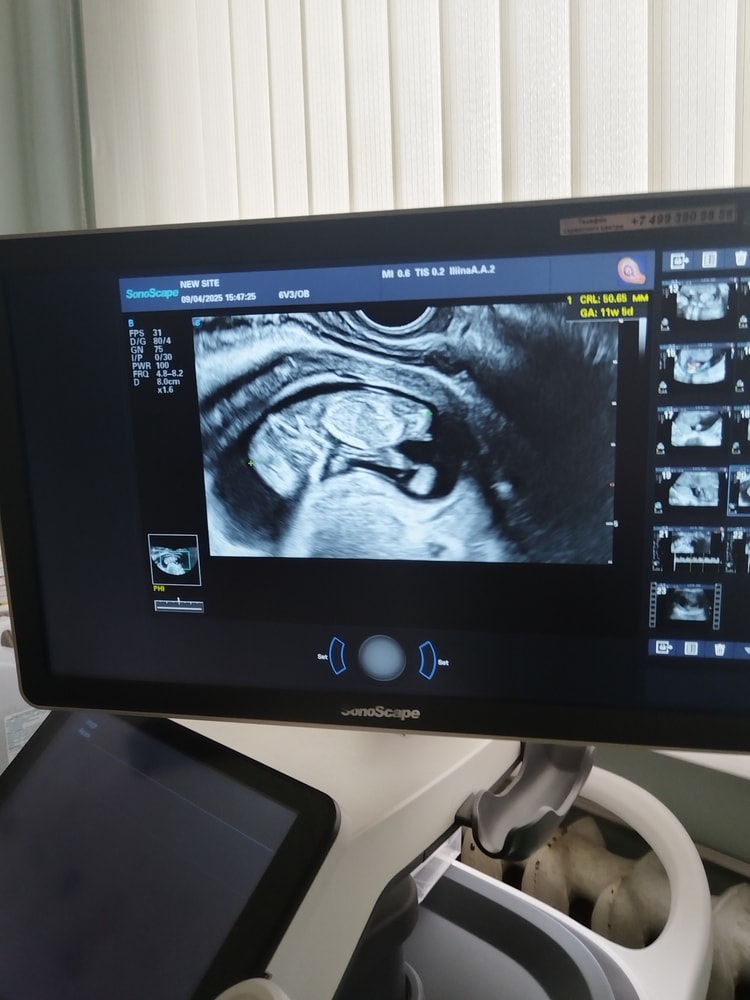

Девочки, кто разбирается. Посмотрите пожалуйста, кто предположительно по бугорку. Изображение

Девочка кажется 🙂🌸